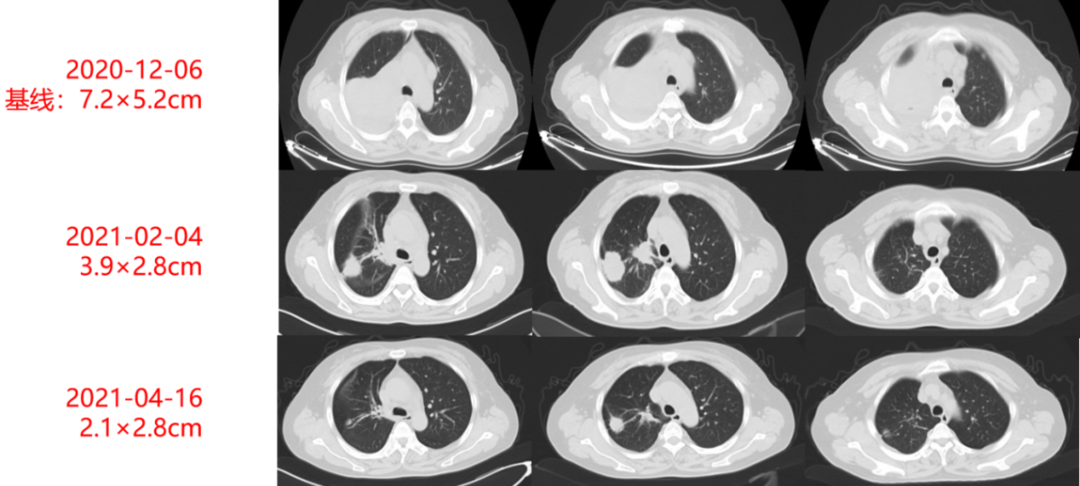

影像学及疗效评价:患者治疗期间定期复查胸部CT,见右肺原发灶逐渐缩小(如图1-2及1-3所示),末次复查时病灶大小为2.1×2.8cm,疗效评价持续PR。

图1-2:治疗期间胸部CT动态变化(肺窗)

图1-3:治疗期间胸部CT动态变化(纵隔窗)

本例患者主因“胸痛1月”就诊,完善相关检查诊断为肺腺癌(T4N2M1,Ⅳ期)伴肺内外多发转移。考虑到患者分期较晚,根治性手术无法切除,先行予患者进行单纯化疗,同时完善基因检测及免疫治疗预测指标,提示患者有TP53基因变异、PD-L1蛋白表达阳性肿瘤细胞占比+(100%),故后续治疗方案调整为化疗+免疫+抗血管生成方案,即培美曲塞+卡铂+替雷利珠单抗+贝伐珠单抗。患者治疗期间规律复查胸部CT,原发病灶体积逐渐缩小(从7.2×5.2cm逐渐缩小至2.1×2.8cm),CEA逐渐降至正常水平(如图1-4所示),疗效持续PR。治疗期间,患者安全性及耐受性良好,未出现明显治疗相关不良反应。